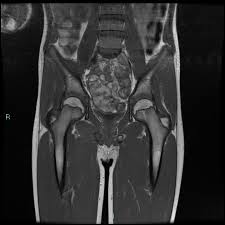

Van neck odelberg disease. Van Neck disease VND is a benign skeletal abnormality of children involving a hyperostosis of the ischiopubic synchondrosis IPS seen on radiographs. BACKGROUND Van Neck disease VND is a benign skeletal abnormality of children involving a hyperostosis of the ischiopubic synchondrosis IPS seen on radiographs. Odelberg disease - Synonym s.

It is characterized by pain in the lower limb due to osteochondritis of the ischiopubic ramus. The van Neck-Odelberg disease is hyperostosis of ischiopubic synchondrosis IPS. Se caracteriza por dolor del miembro inferior debido a osteocondritis de la rama isquiopubiana 12.

Patients typically complain of vague groin or buttock pain. The synchondrosis ischiopubic SIP is the cartilaginous union between the lower ischium and pubis branch in infancy. Left leg dominant patient presented with pain in groin and limping with left leg dominance.